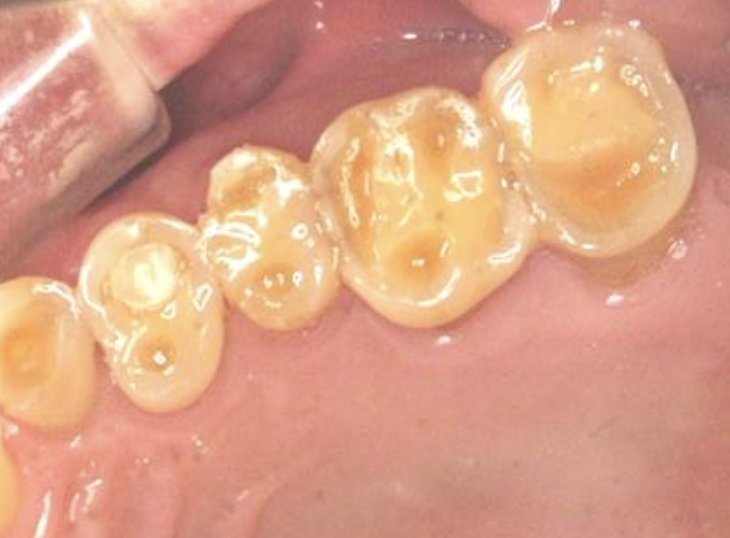

歯の表面のエナメル質が強い力によりすり減ることで内部の象牙質がクレーター上に露出しています。人によってはものが詰まりやすくなった、歯がしみる、噛むと痛むといった症状が出ます。